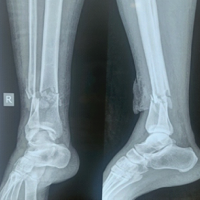

The patient was a 23-year-old right-hand dominant female preschool teacher who sustained a crush injury to the right hand and arm when she was riding in an ATV that rolled over. She was seen at a local trauma center and discharged in a splint. The patient presented to the clinic 3 weeks post-injury with complaints of numbness and tingling in the radial digits and diffuse swelling of the hand. Radiographs and a CT scan of the right hand were performed, which demonstrated right second and third CMC fracture dislocations, right fourth metacarpal base and capitate fractures, and a right displaced ulna shaft fracture (Fig. 1 and 2). There was also concern for acute carpal tunnel syndrome due to the numbness in the radial digits. Surgery was recommended for fixation of the second and third metacarpal fracture dislocations and capitate, as well as carpal tunnel release.

Figure 1: Pre-operative radiographs of the right hand in splint (a) oblique view, (b) lateral view, and (c) posteroanterior view. X-rays show second and third carpometacarpal base fracture dislocations, fourth metacarpal base and capitate fractures, and displaced ulna shaft fracture.